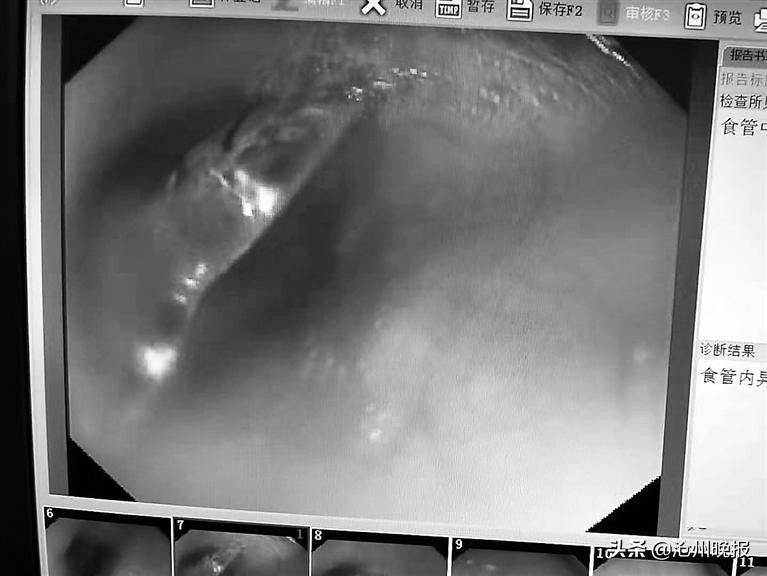

市中心医院儿童院区小儿窥镜室主任张会武说,通过胃镜探查,他发现哲哲食管中下端卡着一个塑料片状的物品。

医生使用工具,将这个塑料片成功取出。

哲哲父母仔细询问孩子,才知道了他误吞贴纸的事情。